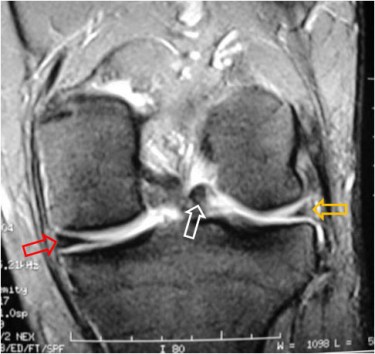

SIGNO DEL MENISCO ROTADO

Signo de rotura meniscal en cortes sagitales de resonancia magnética. El fragmento roto emigra anteriormente y se coloca sobre el cuerno anterior, lo que da una imagen de cuerno anterior anormalmente alto (mayor de 6 mm).

Corte coronal del mismo paciente en el que se observa la asimetría de los meniscos por rotura del externo (flecha amarilla) y la posición anómala del fragmento medial (flecha blanca). La flecha roja señala el menisco normal.